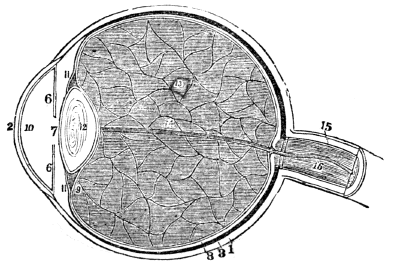

| 44. | Anatomy of the Organs of Vision, | 394 |

| 45. | Physiology of the Organs of Vision, | 404 |